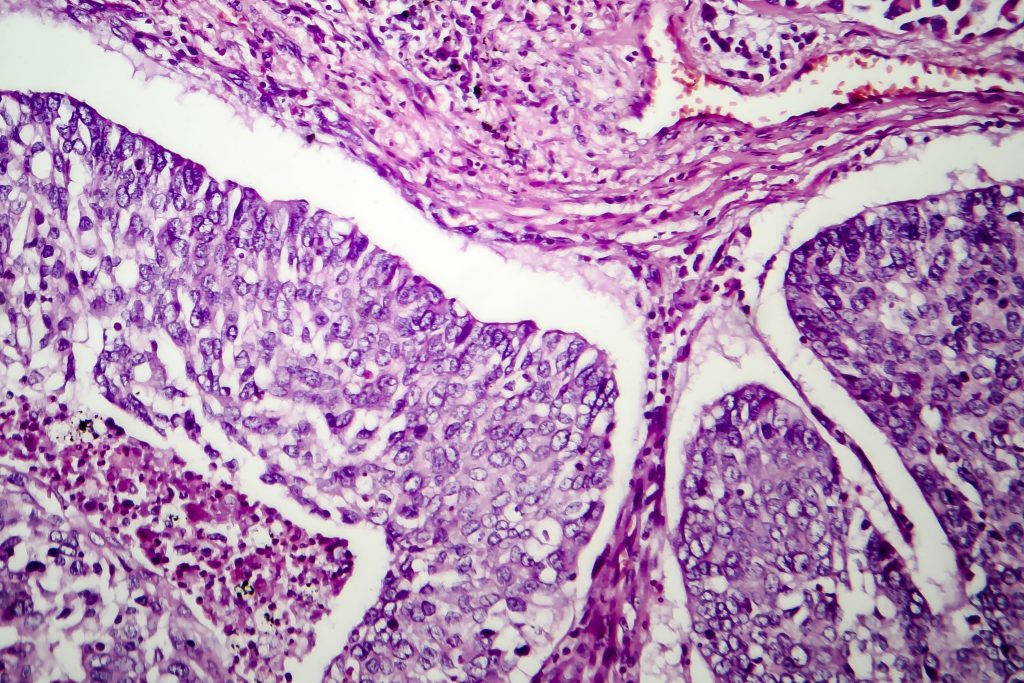

Histology

IMD proudly offers the following Histology Services to its patients, clients, and customers in a highly efficient specimen turnaround time and high quality work.